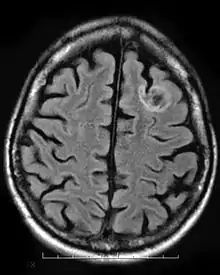

Tumeur neuroépithéliale dysembryoplasique (TNT)

Une tumeur neuroépithéliale dysembryoplasique est une tumeur bénigne rare qui touche les enfants et les adolescents de moins de vingt ans. La tumeur se produit dans le tissu recouvrant le cerveau et la moelle épinière. Les symptômes de la tumeur dépendent de sa localisation, mais la plupart des enfants souffrent de crises qui ne peuvent être contrôlées par des médicaments. Elle est généralement traité par chirurgie invasive et les patients sont généralement capables de récupérer complètement, avec peu ou pas d'effets à long terme[9].

Les kystes neuroépithéliaux, également appelés kystes colloïdes, se développent chez les personnes âgées de 20 à 50 ans et sont relativement rares chez les personnes de moins de vingt ans. Les kystes sont des tumeurs bénignes qui apparaissent généralement dans le troisième ventricule antérieur. Les kystes se produisent dans l'épithélium, ce qui expose leurs patients à un risque d'hydrocéphalie obstructive, d'augmentation de la pression intracrânienne et, rarement, d'hémorragie intrakystique. Cela résulte de l'agrandissement des kystes en provoquant la sécrétion de liquide mucineux supplémentaire par l'épithélium. Les kystes sont généralement découverts fortuitement ou si les patients deviennent symptomatiques présentant les symptômes de l'hydrocéphalie. Les kystes les plus gros sont opérés tandis que les kystes plus petits qui ne sont pas obstructifs peuvent être laissés seuls[10].

Les tumeurs oligodendrogliales se manifestent dans les cellules gliales, qui sont chargées de soutenir et de protéger les cellules nerveuses du cerveau. La tumeur se développe sur oligodendrocytes et se trouve généralement dans le cerveau autour des frontaux ou temporels lobes. Les tumeurs peuvent soit se développer lentement de manière bien différenciée, retardant l'apparition des symptômes, soit se développer rapidement pour former un oligodendrogliome anaplasique. Les symptômes de ce type de tumeur comprennent des maux de tête et des problèmes visuels. De plus, le blocage des ventricules pourrait provoquer une accumulation de liquide céphalo-rachidien entraînant un gonflement autour de la tumeur. L'emplacement de la tumeur peut également affecter les symptômes, car les tumeurs du lobe frontal peuvent provoquer des changements progressifs de l'humeur ou de la personnalité, tandis que les tumeurs du lobe temporal entraînent des problèmes de coordination et d'élocution[11].